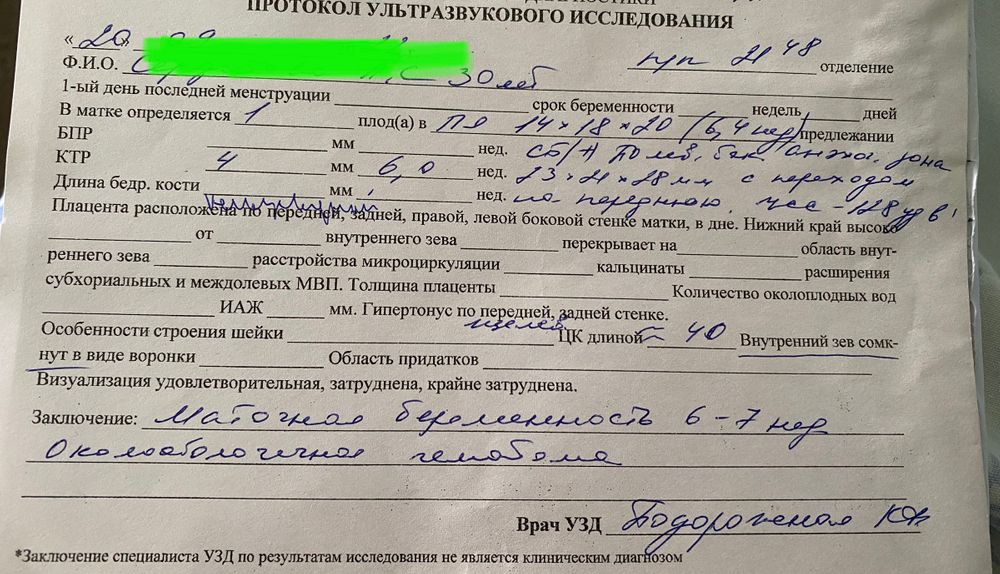

Узи. Потеряла надежду. Чего ждать? Что делать?

сделали по животу узи, сказали с такой отслойкой шансов мало, огромная круглая и больше ПЯ.

что правда все так плохо по узи!!??? У кого беременность продолжила развиваться несмотря на огромную отслойку????

еще смущает ктр немного. Не маловат?